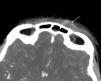

En los estudios de laboratorio destacan proteína C reactiva 331mg/L, procalcitonina 105,5 ng/mL, gammaglutamil transpeptidasa 159 UI/L, sodio 127 mEq/L y cloro 96 mEq/L, con aumento de fibrinógeno (665mg/dL). En el hemograma: leucocitosis (21,6×10e9/L), con desviación izquierda (neutrofilia 90%). Se realiza una TC craneal con contraste, evidenciando colección subperióstica en el margen nasal de la órbita izquierda y en el tejido celular subcutáneo de 17×8mm con realce periférico. Trombosis de la vena angular izquierda, con extensión a la vena orbitaria superior que no alcanza el seno cavernoso, con ingurgitación de los vasos conjuntivales relacionada con la trombosis. Ocupación de senos frontales, maxilares y esfenoidal derecho y parcial de celdillas etmoidales y mastoideas (figs. 2 y 3).